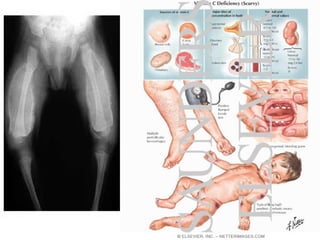

Rickets

• Rickets is the softening and

weakening of bones in children,

usually because of an extreme and

prolonged vitamin D deficiency.

• Some skeletal deformities caused by

rickets may need corrective

surgery.

Scurvy

• The human body lacks the ability to

synthesize and make vitamin C and

therefore depends on exogenous dietary

sources to meet vitamin C needs.

Consumption of fruits and vegetables or

diets fortified with vitamin C are essential

to avoid ascorbic acid deficiency. Even

though scurvy is uncommon, it still occurs

and can affect adults and children who

have chronic dietary vitamin C deficiency.